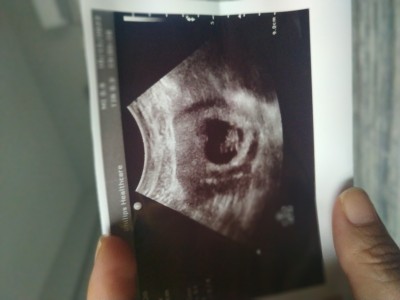

Duruşa göre cinsiyet tahmini yapabilir misiniz önce sağlıklı sonra da hayırlı bir kız evlat istiyorum 2 oğlum var

Gebelik haftası Dokuz

Valla cinsiyeti için bişey diyemicem ama kese kalp şeklinde maşallah çok tatlı bir görüntü

Brz erken cnm ya hiç belli olmuyo

Kiz bebek gorunuyormuki durusunude goreyim)))daha cokk minnak 1 2haftaya gidince ellerini ayaklarini filan rahat goreceksin o zaman atarsin .tahmin ederler kide ben inanmiyorum durusa bilmem yapiya gore soylenilenlere doktor en dogrusunu soyler sana.bende 11haftam doluyor.bi dahaki doktora gidisim 13 14 arasi olacak net soylicem dedi doktor.ozelde